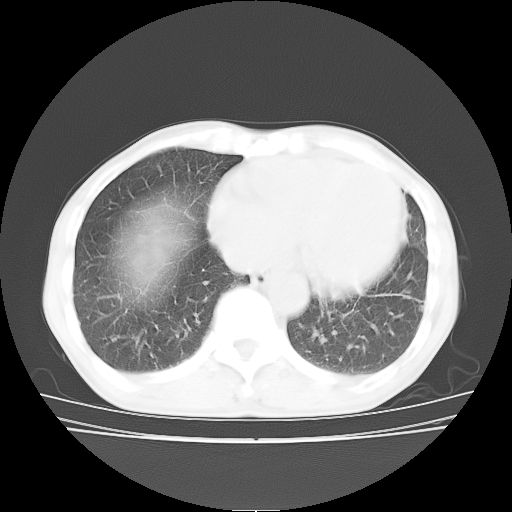

标题: CT25795:感冒后反复咳嗽两月余,痰中带血半月余。X诊断“肺 [打印本页]

标题: CT25795:感冒后反复咳嗽两月余,痰中带血半月余。X诊断“肺

1.双肺肺梗塞(理由:病灶呈三角形,与胸膜相连且局部胸膜肥厚,左心室增大)伴肺感染。

考虑两肺感染性病变,左肺上叶舌段肿瘤性病变待排;建议抗炎治疗后复查。